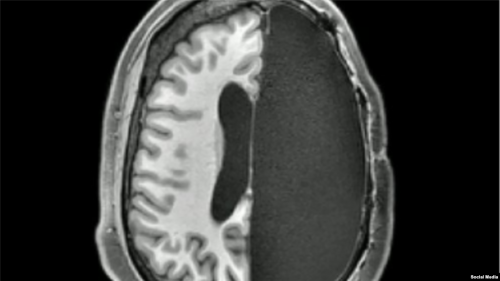

دراسات جديدة: اكتشاف مذهل.. ماذا يحدث بعد إزالة نصف الدماغ؟ أظهرت مسوحات جديدة أن أدمغة البشر التي تم استئصال نصفها خلال مرحلة الطفولة، تستطيع مواصلة نشاطها ب...